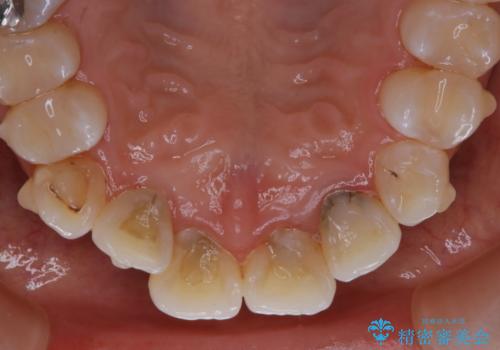

インビザライン矯正治療中のPMTC

- インビザライン中にクリーニングを希望とのことでした。PMTC30分コースを行いました。

矯正治療中は虫歯や歯周病リスクが高くなります。

インビザライン矯正治療はマウスピースを長時間使用するため、歯石や汚れなどが付着したままだと、フィットが悪くなったり、口臭が強く出たりする原因につながることもあります。

定期的にPMTCを行うことをおすすめします。